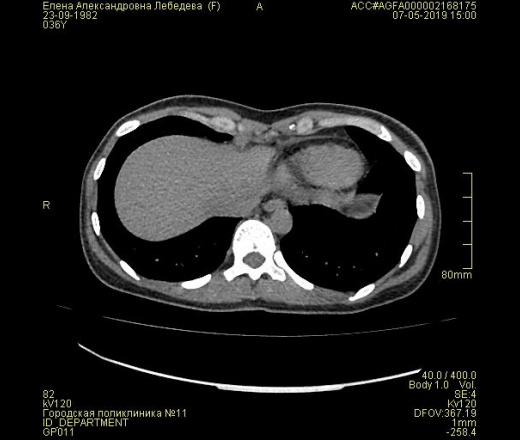

Образование, нарост на ребра грудной клетки слева. Узи видит, КТ нет.

Прошу Вас проконсультировать меня по результатам КТ нароста на ребре грудной клетки.

Нарост пульпируется и болит. Появилась тахикардия в покое. Сердце проверила. Норма.

Узи показало уплотнение ребра грудной клетки  слева. КТ прилагаю.

А зачем на 26 дней поставили? Результат только в конце месяца получите. Хотелось бы знать какое ребро и в к аком иесте. Ничего плохого не вижу.

Никаких наростов не видно, вот картинка,.

То же ничего страшного, кроме фрагментарного обызвествления хрящей ребер, что не является патологией, не нашел.

Добрый день, спасибо большое за Ваш ответ. Подаскажите пожалуйста возможно ли увеличение фрагментарного обызвествления хрящей ребер в моем случае? Потому что оно выросло в размере. Раньше надо было прощупывать а сейчас достаточно приложить руку и уплотнение выпирает.